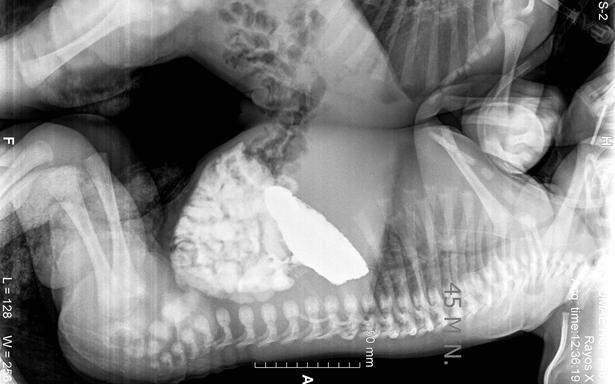

La cesárea se programó para el día 15 de diciembre de 2017; ambos nacieron sin complicaciones, pesaron poco más de cinco kilogramos, con una talla de 45 centímetros.

Tras diversos exámenes de tomografía, ecocardiograma y resonancia magnética, cuando los niños cumplieron 41 días de vida, fueron programados para la cirugía que los separaría.